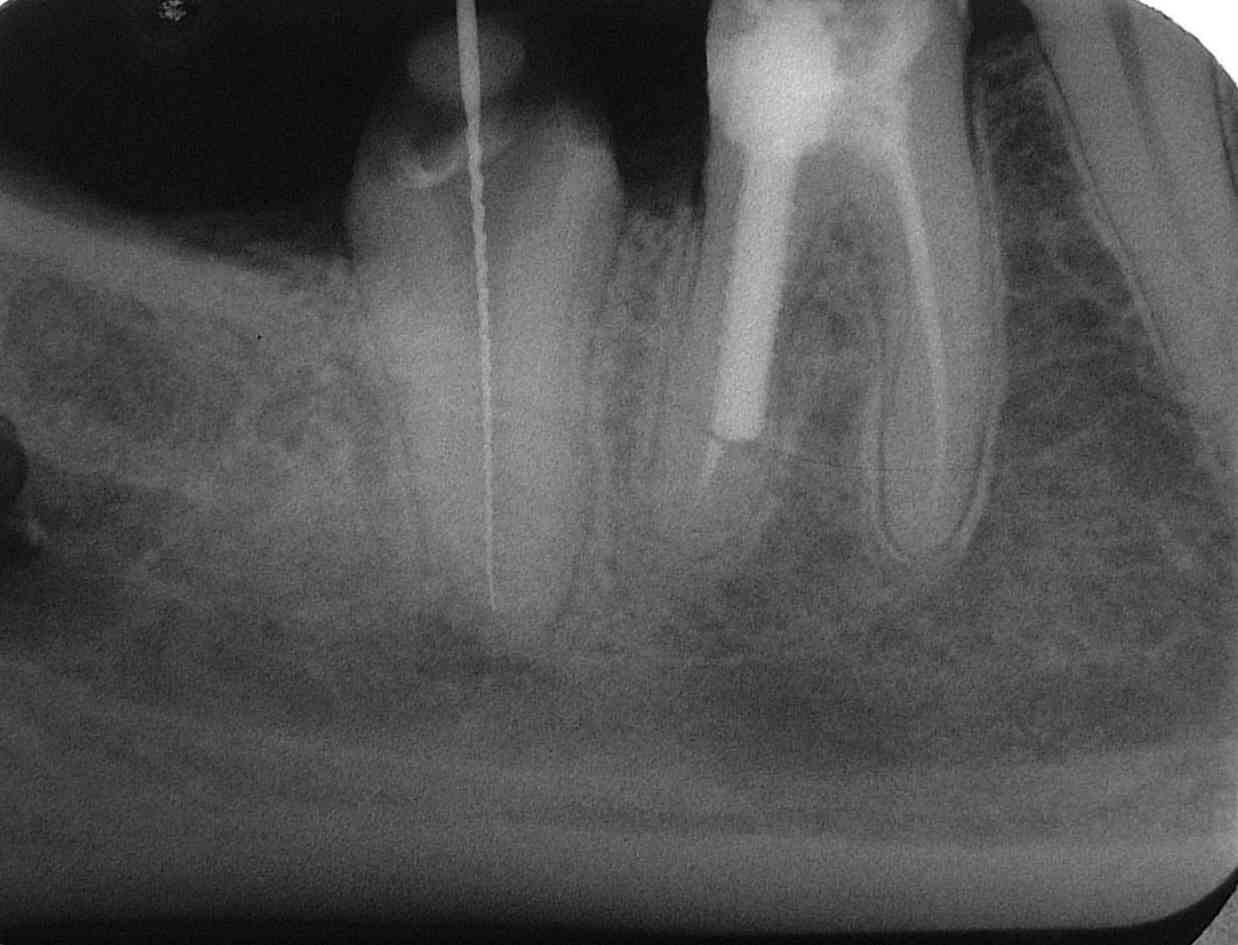

Messaufnahme an 47 im März 1996. Auch bei leicht veränderter Röntgenachse imponiert der Stift an 46 regelrecht (Klick!)

Kontrolle nach WF an 47 unmittelbar vor prothetischer Versorgung im Juni 1996 (Klick!)